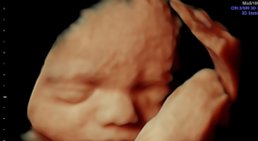

3D/4D Ultraschall

Bei meinen Patientinnen wird bei guter Kindslage auf Wunsch auch ein 3D Bild angefertigt.

Aus Termingründen ist es mir NICHT möglich für "ordinationsfremde"...